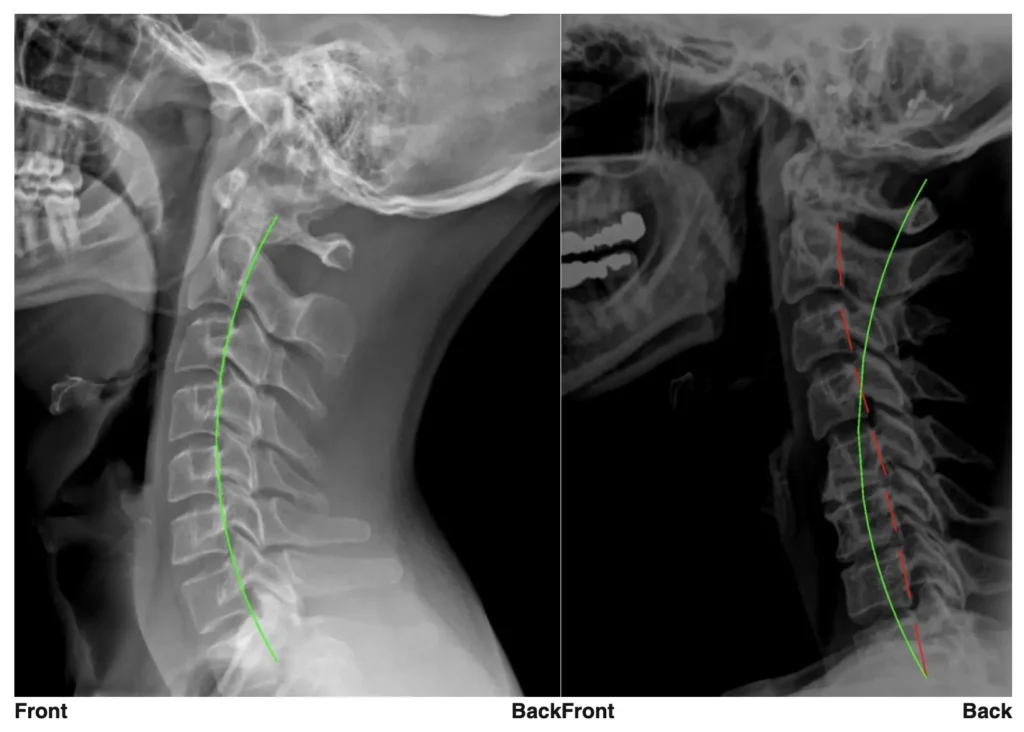

Precise X-Ray Reports

We use state-of-the-art technology from PostureRay to visualize your digital x-rays to measure spinal alignment and determine exactly what type of care is right for you.